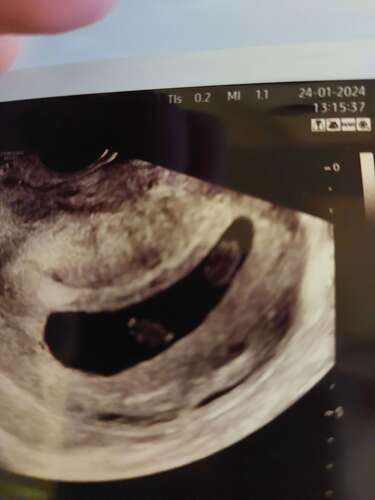

Gefeliciteerd met je zwangerschap!

Ik heb vorig jaar een eeneiige tweeling gekregen die alles deelde.

Wij kwamen er met 5 weken al achter.

Wij kwamen er ook tijdens de eerste echo achter dat we een een-eiige tweeling verwachten. Zelfde als bij jou. Door onze eigen Fertiliteitspoli doorverwezen maar het AMC. met 12 weken daar een uitgebreide echo gehad. En wat bleek: Tussen onze tweeling zit toch een tussenvliesje. Onze tweeling deelt dus wel de placenta, maar niet de vruchtzak. Op de echo met 7 weken was dit dus ook echt niet zichtbaar.

Gefeliciteerd wat leuk!! Hier ook zwanger van een eeneiige tweeling 馃槏 Bij onze eerste echo dachten ze ook dat ze alles deelden dus gelijk in de stress maar geluk bij de tweede echo al snel duidelijk dat ze placenta delen maar wel eigen vruchtzak hebben gelukkig! Geniet van je zwangerschap 馃グ